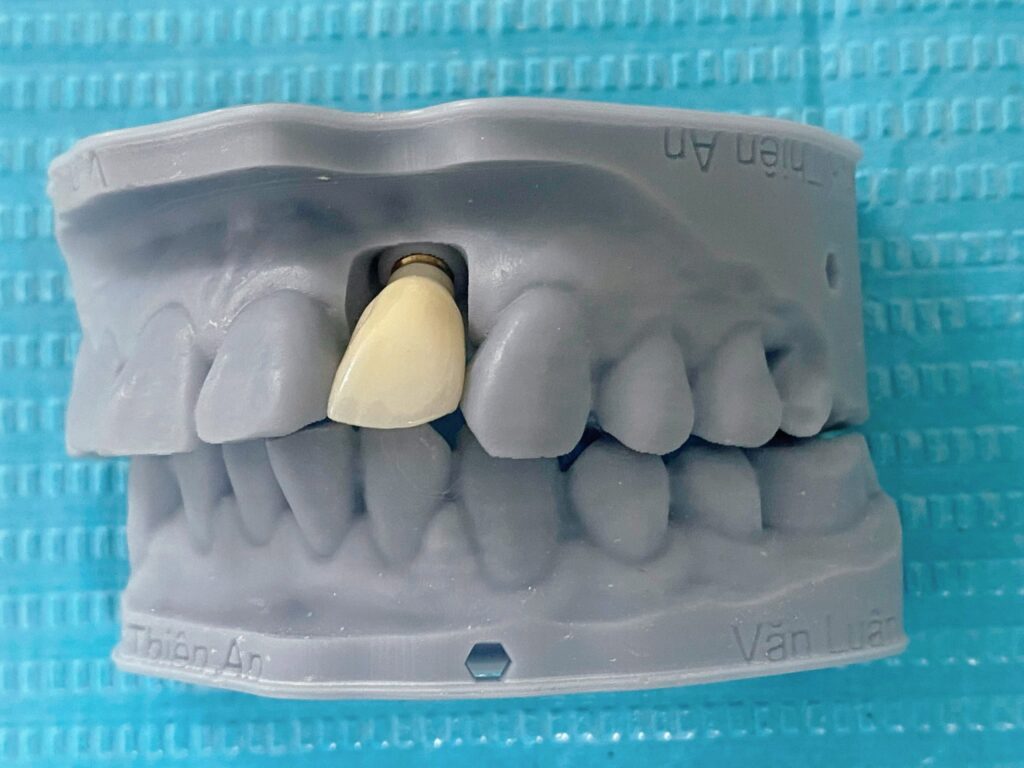

Tiếp tục là một ca cấy ghép implant vùng răng cửa bên tại nha khoa Thiện An BMT – Đăk Lăk cho anh L. (35 tuổi). Ưu điểm của phương pháp này là sẽ duy trì được chiều cao và độ dày của vùng xương ổ răng mất, ổn định theo thời gian với độ thẩm mĩ gần như răng thật mà các phương pháp khác như cầu răng sứ hoặc hàm giả tháo lắp không làm được

Next is an implant surgery in the lateral incisor area at Thien An BMT Dental Clinic – Dak Lak for Mr. L. (35 years old). The advantage of this method is that it will maintain the height and thickness of the lost alveolar bone area, stable over time with an aesthetic almost similar to real teeth that other methods such as porcelain bridges or removable dentures can’t achieve